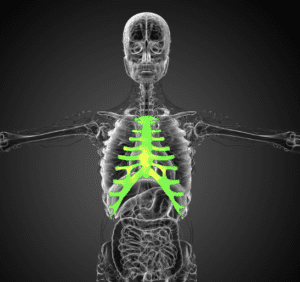

Imagine—just for a moment—finding yourself in the dizzying aftermath of a crash, the sudden, suffocating pain in your chest impossible to ignore. A broken sternum, that sturdy bone anchoring ribs and shielding the heart, isn’t just a fracture; it’s a life-interrupting ordeal. For many, this injury means more than mere discomfort. It can spell lost time, drained bank accounts, and, perhaps worst of all, altered futures.

When this central bone snaps, it’s no small affair. You’re looking at swelling, bruising, and an unrelenting ache that makes breathing feel like a challenge. Even the slightest movement can feel like fire. It’s an injury often born of blunt force—maybe a direct smack against the steering wheel or the firm grip of a seatbelt holding you back, bracing against impact. What are the signs? Well, apart from the pain: shortness of breath, tenderness, and yes, often a nasty bruise marking the chest.